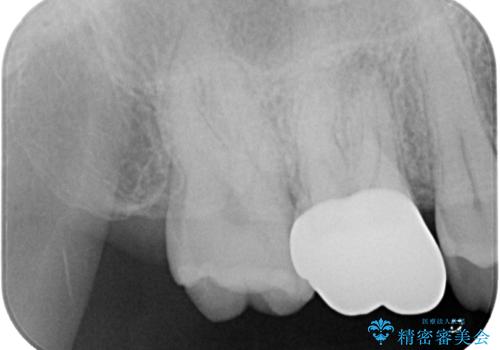

- セラミックの詰め物が割れたとのことで来院された患者様です。現在に至るまで二度セラミックの詰めもの(セラミックインレー)が割れていて、噛み合わせも強い方なのでフルジルコニアクラウンとゴールドクラウン(PGAクラウン)を治療方法としてご提案しました。

拡大鏡視野下で保険のプラスチック(コンポジットレジン)、虫歯を除去し、フルジルコニアクラウン、に適した形にしました。

歯と歯茎の間に圧排糸と呼ばれる糸を入れてシリコーン印象を行いました。

噛み合わせが強いので今後はナイトガードを使ってもらいながらメンテナンスで通ってもらい経過を診ていく予定です。